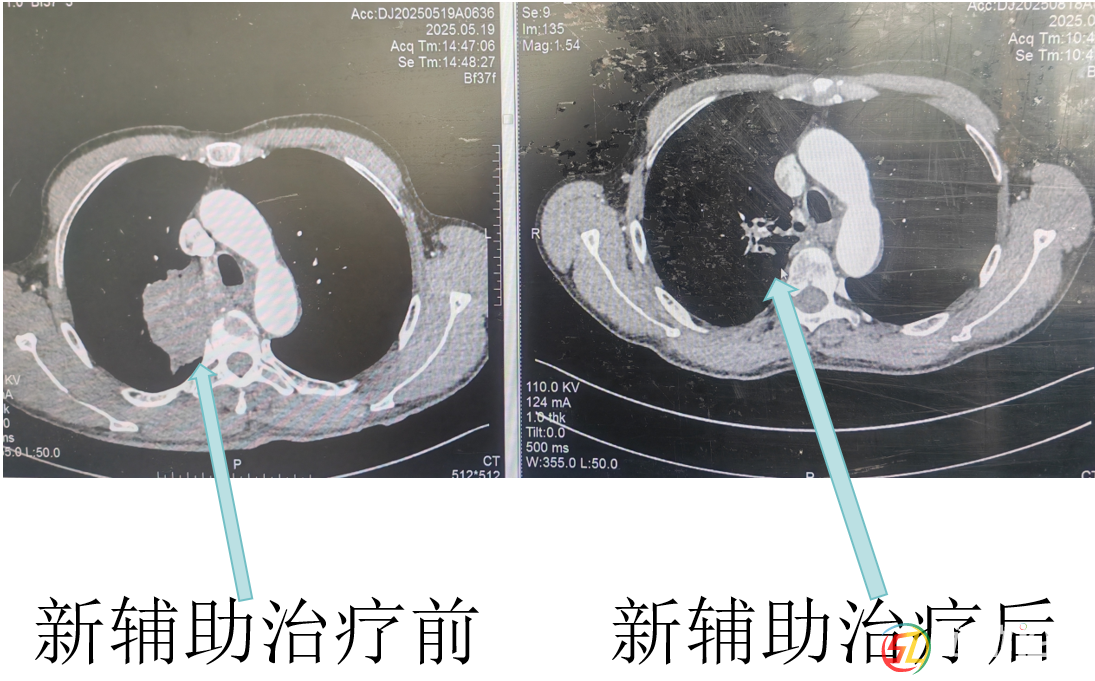

經(jīng)呼吸與危重癥醫(yī)學科醫(yī)生杜鵑三個周期的藥物治療后,復(fù)查CT顯示羅大爺肺上的腫瘤明顯縮小了!彭均偉判斷,現(xiàn)在手術(shù)有望完整切除腫瘤。就在大家看到希望時,新的問題出現(xiàn)了。羅大爺有幾十年的老慢支和哮喘病史,肺功能檢查結(jié)果很差,根本達不到肺葉切除的手術(shù)標準。而且他三年前還因為心臟病做過冠脈支架手術(shù),長期服用阿司匹林,這又增加了手術(shù)出血風險。面對這些困難,彭均偉先為羅大爺制定了詳細的肺功能康復(fù)計劃,經(jīng)過一段時間的精心調(diào)理,羅大爺?shù)姆喂δ芙K于提升到了可以接受手術(shù)的水平。

手術(shù)當天,彭均偉醫(yī)師團隊憑借豐富的胸腔鏡手術(shù)經(jīng)驗,先處理好肺部的血管和支氣管,再仔細分離粘連區(qū)域,成功切除了右上肺葉,并清掃了周圍的淋巴結(jié)。術(shù)后病理結(jié)果帶來了更大的驚喜:腫瘤細胞已經(jīng)完全消失,連之前轉(zhuǎn)移的淋巴結(jié)也轉(zhuǎn)為陰性!這意味著羅大爺通過“轉(zhuǎn)化治療+手術(shù)”的新模式,達到了病理學上的完全緩解。